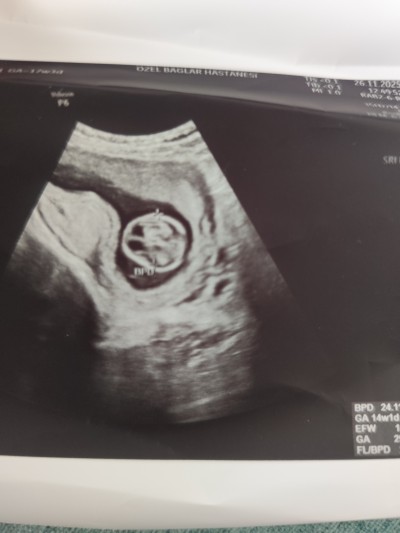

26 Kasım 2025 Hamilelik Dönemi Genel kategorisinde (63 puan) sordu

Merhaba arkadaşlar bugün ultrason girdim kontrole doktor bana bebeğin başında boşluk var öyle olup düzelme ihtimali var mı